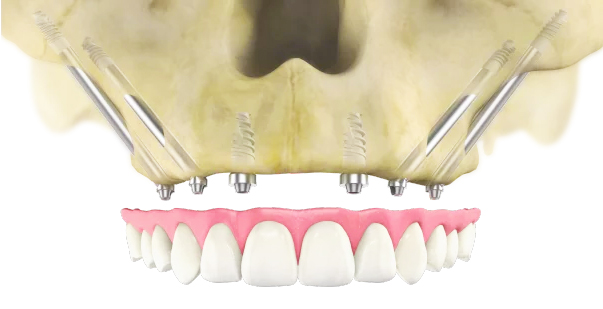

Zygomatic implants are a type of dental implant specifically designed for patients with severe bone loss in the upper jaw. Unlike traditional implants that are anchored into the jawbone, zygomatic implants are longer and are anchored into the zygoma, or cheekbone. This provides a stable and robust foundation for dental prosthetics, even in cases where the upper jawbone is insufficient to support conventional implants.

Zygomatic implants can often be placed without the need for bone grafting, making them a quicker and less invasive solution for patients with significant bone loss. This innovative approach allows for full-mouth rehabilitation, restoring function and aesthetics for individuals who might otherwise be unable to receive dental implants.

Zygomatic implants work by anchoring into the zygoma, or cheekbone, rather than the maxillary bone of the upper jaw. The procedure begins with a thorough evaluation, including imaging studies like CT scans, to assess the bone structure and plan the implant placement. The implants themselves are longer than traditional dental implants, designed to reach the dense zygomatic bone.

During surgery, the implants are inserted through the alveolar crest and anchored into the zygoma, providing a stable base for prosthetic teeth. This anchorage allows for immediate loading, meaning that temporary prosthetics can often be placed on the same day of the surgery. Over time, the implants integrate with the bone through a process called osseointegration, ensuring long-term stability and functionality.